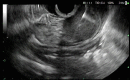

Rare Subepithelial Mass Diagnosed as Gastric Splenosis via EUS-FNA